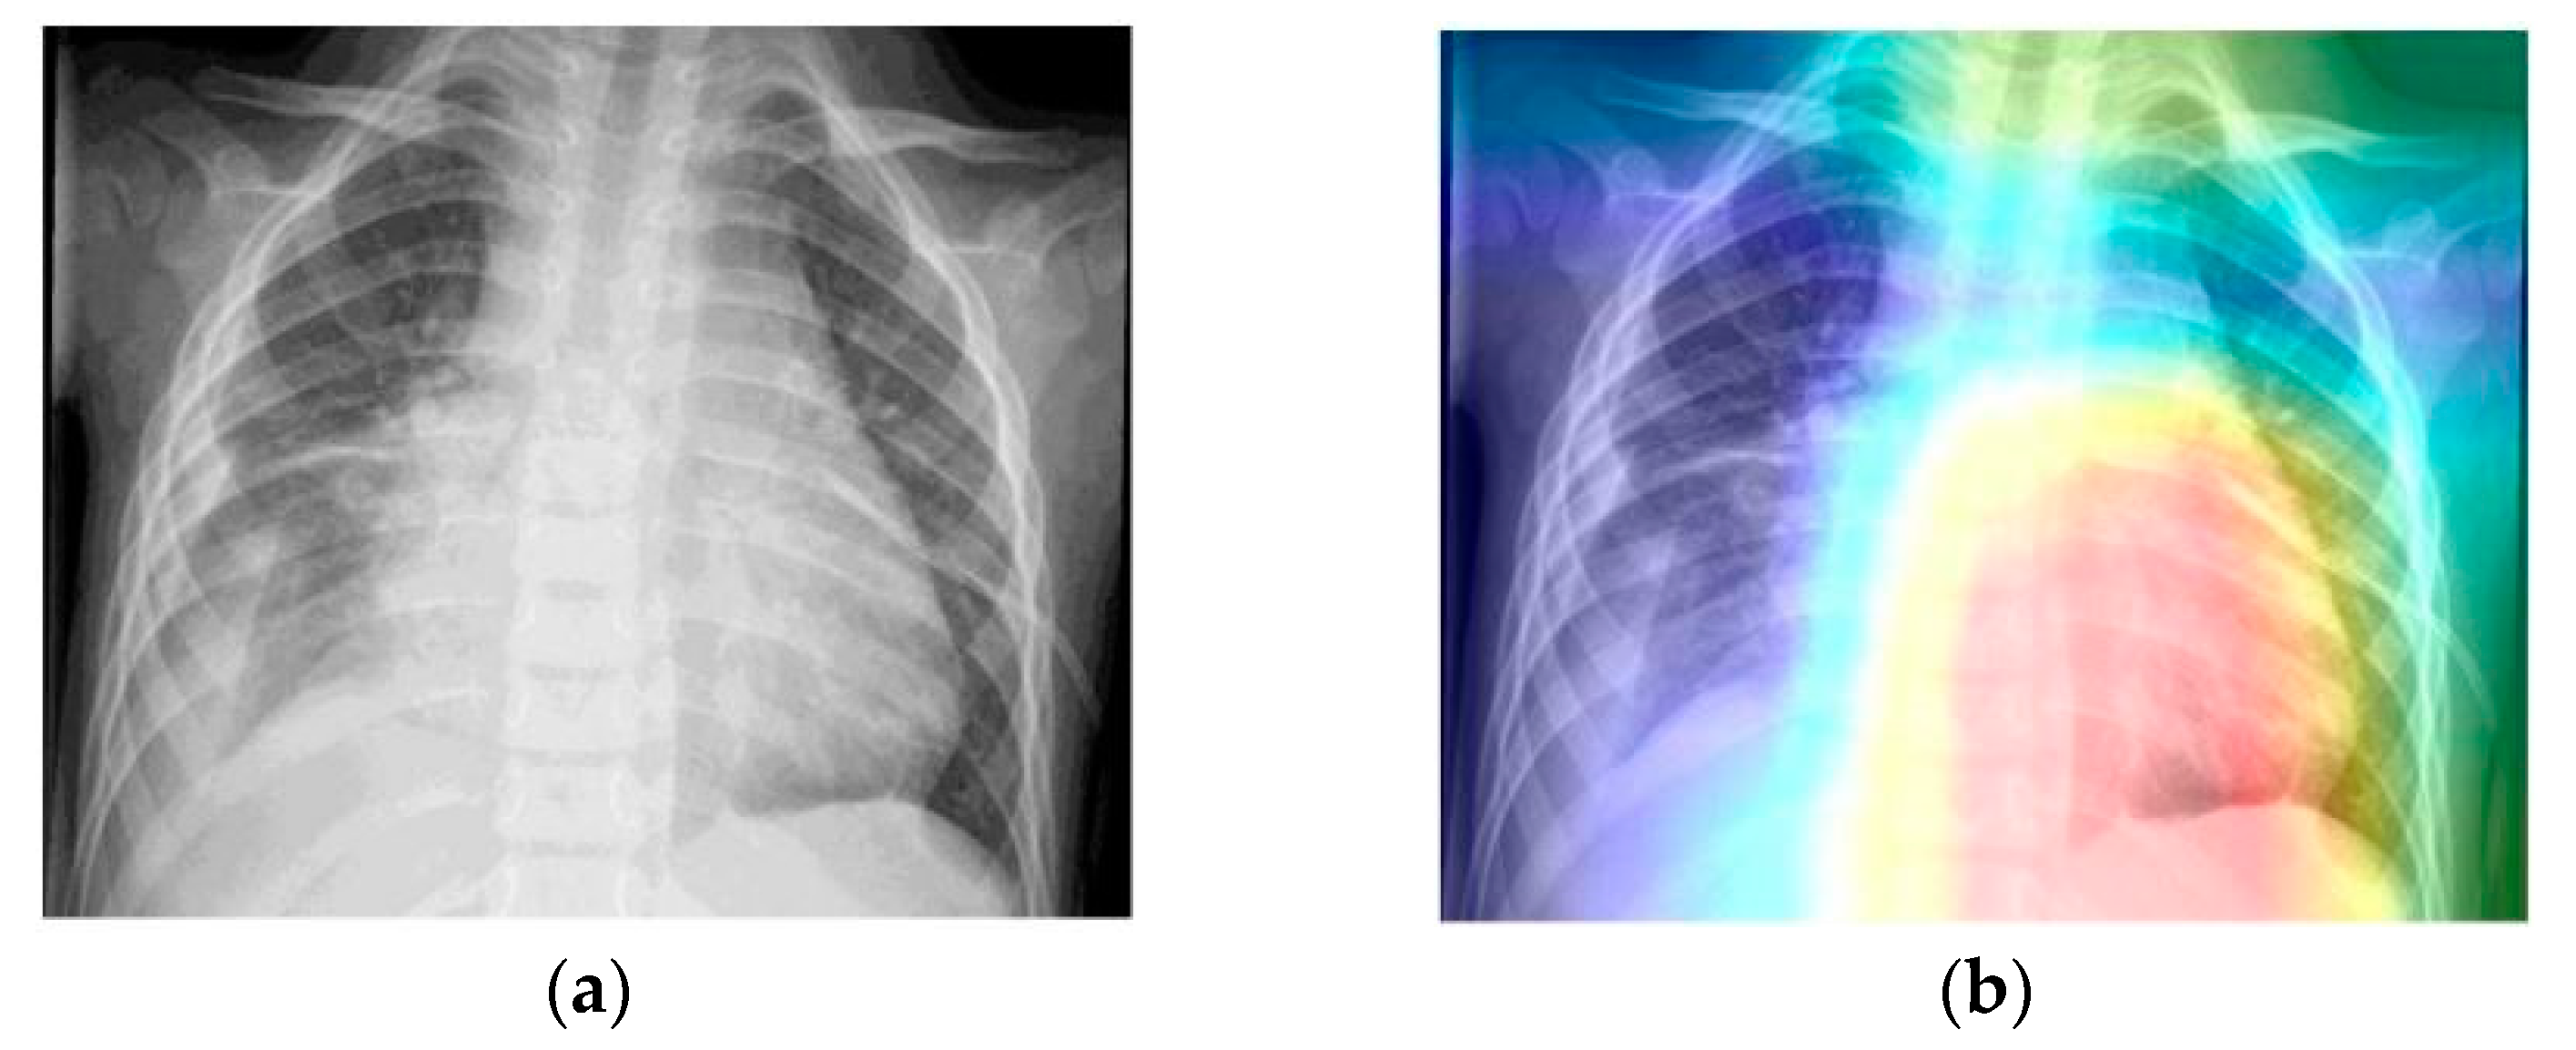

- Grad-CAM was used in order to generate a heatmap of the possible localization of pneumonia manifestations on test images.

6. Discussion

- Selvaraju, R.R.; Cogswell, M.; Das, A.; Vedantam, R.; Parikh, D.; Batra, D. Grad-CAM: Visual Explanations from Deep Networks via Gradient-based Localization. Int. J. Comput. Vis. 2020, 128, 336–359. [Google Scholar] [CrossRef]